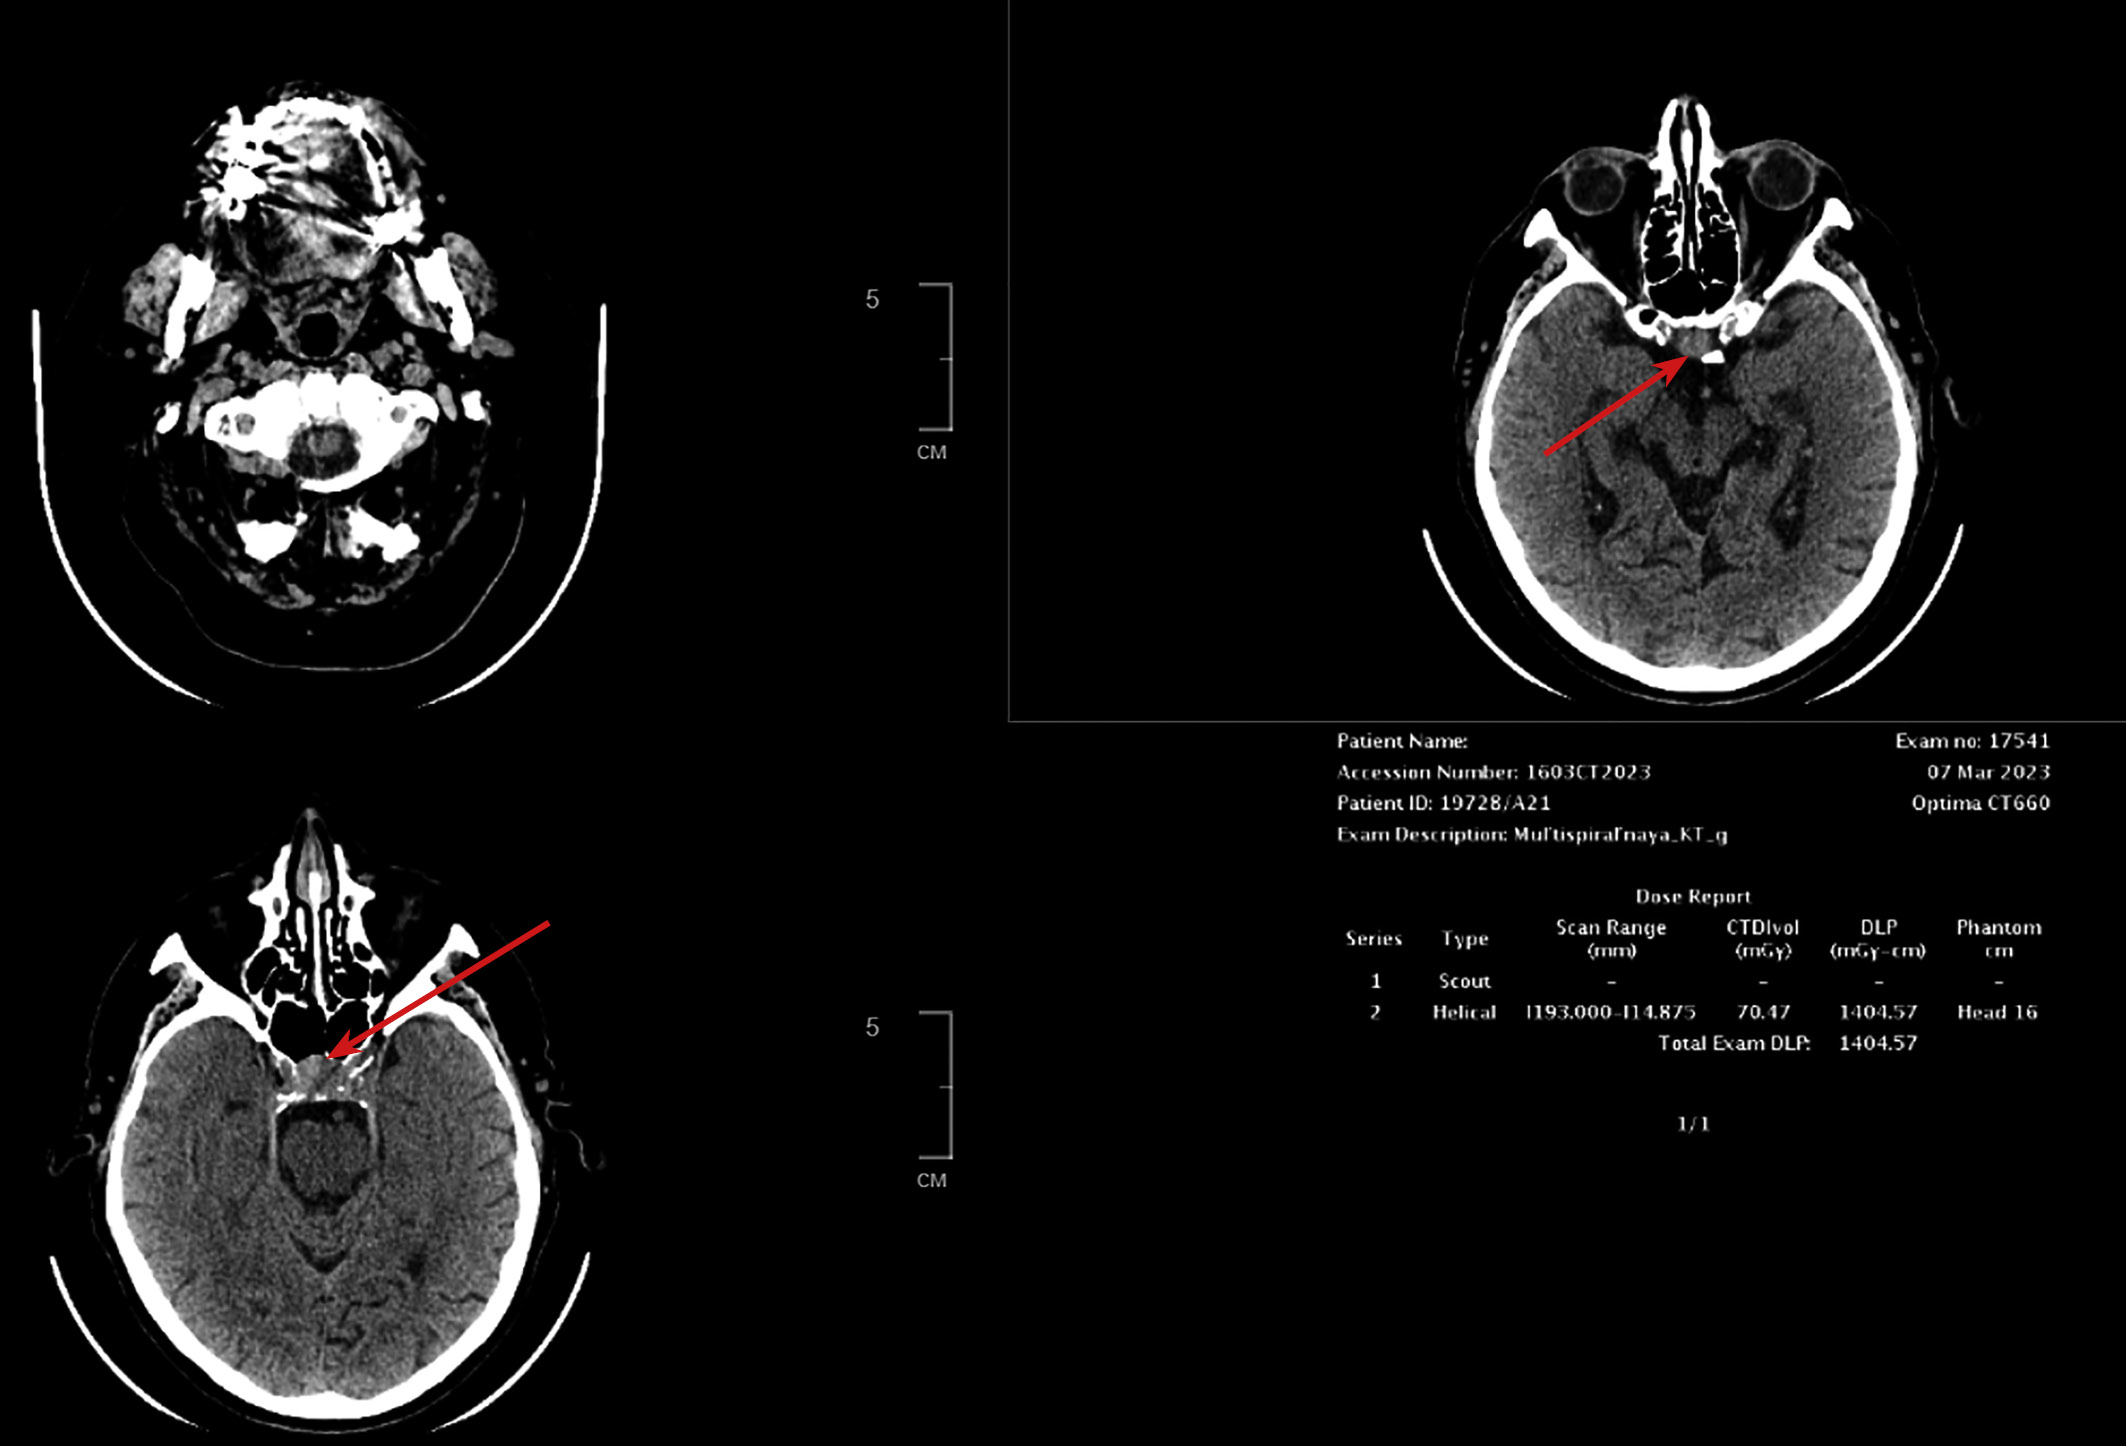

Пациент Г., мужчина 73 лет, отметил появление выраженных зрительных нарушений (снижение остроты зрения на левый глаза, двоение) с последующим ухудшением. Данная симптоматика возникла через 6 лет после радикальной левосторонней нефрэктомии в 2017 г., выполненной по поводу светлоклеточного почечноклеточного рака (рТ2N0M0). По данным компьютерной томографии через 4 года (2021 г.), выявлена опухоль в правой почке 14х15х14 мм солидной структуры. В январе 2022 г. в связи с потерей сознания госпитализирован в городскую больницу по месту жительства, где диагностирована вторичная надпочечниковая недостаточность. Назначена заместительная терапия препаратами преднизолона. Впервые в феврале 2022 г. выполнена КТ головного мозга, обнаружены признаки объемного образования хиазмально-селлярной области, пролабирующего через верхнюю апертуру турецкого седла с ровными контурами, размером 10х12х14 мм, параселлярные структуры без особенностей. МРТ не проводилась в связи с клаустрофобией у пациента. Во время госпитализации в ГНЦ ФГБУ НМИЦ эндокринологии в марте 2022 г. подтверждена вторичная надпочечниковая недостаточность (АКТГ <5,00 пг/мл (0–46), кортизол <1,00 мкг/дл (5–25), а также установлен гипогонадотропный гипогонадизм (тестостерон — 3,22 нг/дл (167–654), ФСГ — 0,32 мМЕ/мл (0,95—11,95). При обследовании была исключена гормональная активность опухоли при наличии умеренного повышения уровня общего пролактина до 1243 мЕд/л, что было интерпретировано как масс-эффект опухоли. По результатам МСКТ забрюшинного пространства с контрастным усилением, данных за рецидив заболевания не получено, сохраняется образование правой почки, без отрицательной динамики. При повторной госпитализации через 1 год (март 2023 г.) отмечалась отрицательная динамика в виде прогрессирования зрительных нарушений и роста образования хиазмально-селлярной области до 18х27х15 мм с признаками сдавления хиазмы и пролабирования в полость 3 желудочка на 7,2 мм, компримируя его передние отделы (рис. 3.1).

Пациент осмотрен офтальмологом, выполнена компьютерная периметрия, выявлено сужение периферической границы поля зрения концентрическое на 10 градусов справа, с височной стороны на 15–20 градусов слева. При обследовании данных за наличие метастазов почечноклеточного рака другой локализации не получено.

Рисунок 3.1. КТ головного мозга.